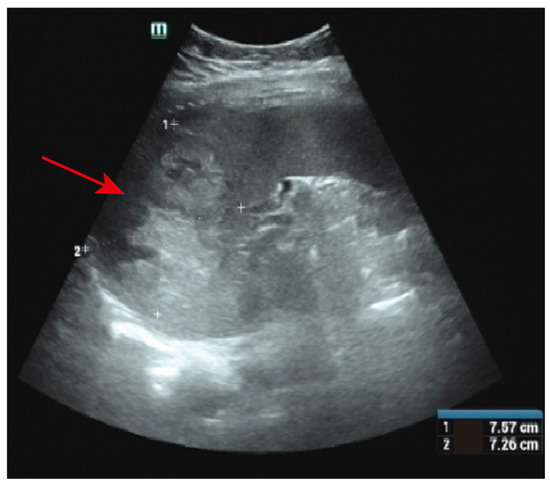

2. Case Description